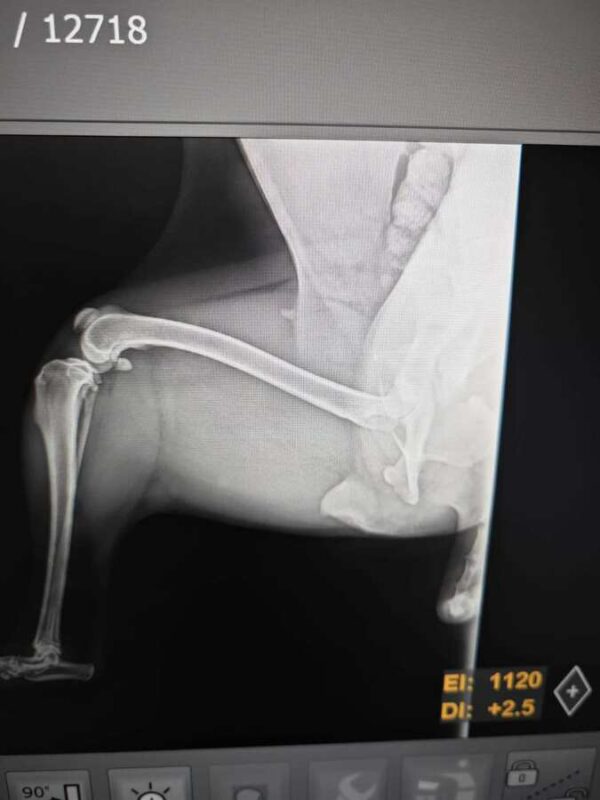

Diese kleine Hündin hatte einen Autounfall und wurde verletzt von den Hundefängern im Tierheim Bucov abgegeben. Nena wurde direkt untersucht und dabei wurde festgestellt, dass ihre linke Hüfte gebrochen ist. Sie wurde umgehend zu Spezialisten in Bukarest gebracht und operiert. Nena ist völlig fertig und unter Schock. Dennoch lässt sie sich vorsichtig anfassen.

hatte Hüft-OP nach Autounfall